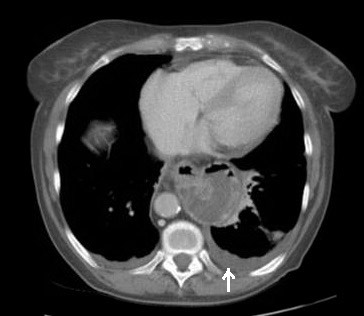

2929. Изменение, обозначенное стрелкой на изображении, указывает на наличие